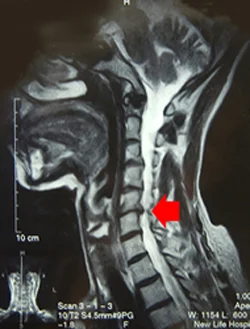

55歳女性(頸部椎間板ヘルニア)

椎間板障害(MRI検査)

娘さんと二人で乗っていた車の後方から衝突されむち打ちになりました。娘さんは何ともないのに、お母さんだけ徐々に悪化して頸部椎間板ヘルニアになりました。

発症後一年で、後遺症認定12級を受けましたが、その後、鍼治療を始めて、一年後にはほとんど症状がなくなりました。同じ速度で衝突されても、首の姿勢の違いでむち打ちが悪化する症例でした。